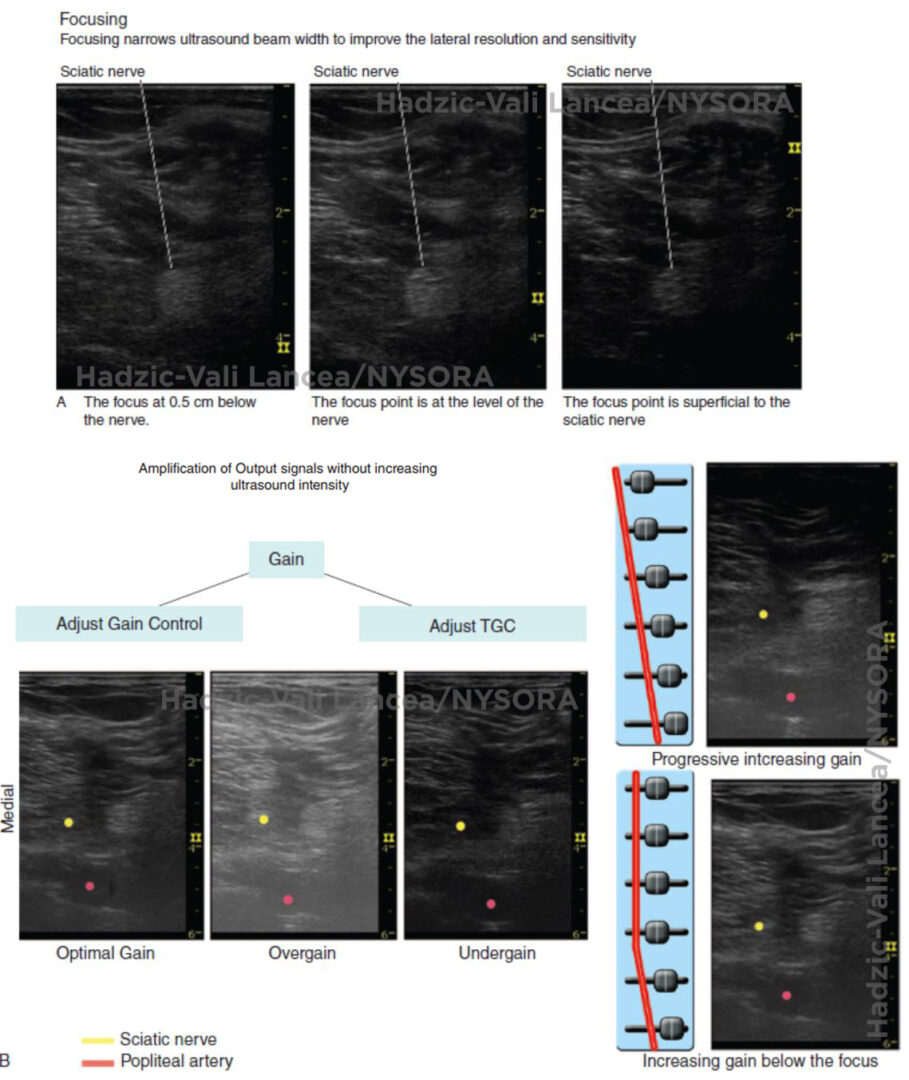

Optimizing an Ultrasound Image NYSORA The New York School of Regional How To Optimize Ultrasound Images optimizing an ultrasound image can be challenging, especially for the new practitioner. by simply testing a few controls, you can quickly gain a basic understanding of ultrasounds and become a master at image optimization. in order to obtain optimal ultrasound images, it is necessary to adjust several parameters continuously during the examination. from a medical as. How To Optimize Ultrasound Images.